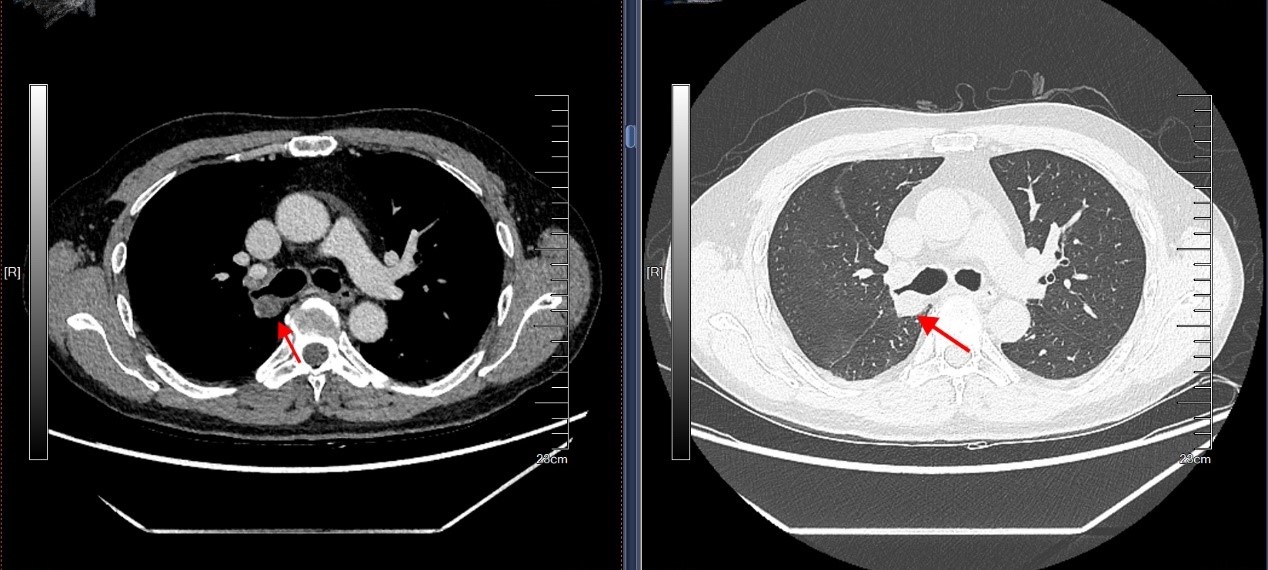

该患者因反复咳嗽、气促就诊,经CT及支气管镜检查,发现右肺主气管内有一约1.7cm的肿物,病理确诊为支气管低度恶性肿瘤。传统手术需切除整个右肺,但考虑到患者肺功能及生活质量,我院胸心大血管外科主任马海涛教授团队决定采用创伤更小的“支气管袖式切除术”——在完整切除肿瘤的同时,将健康支气管断端吻合,最大限度保留健康肺组织。手术历时3小时余,术中快速病理确认切缘无肿瘤残留。术后患者未出现并发症,肺功能恢复理想。